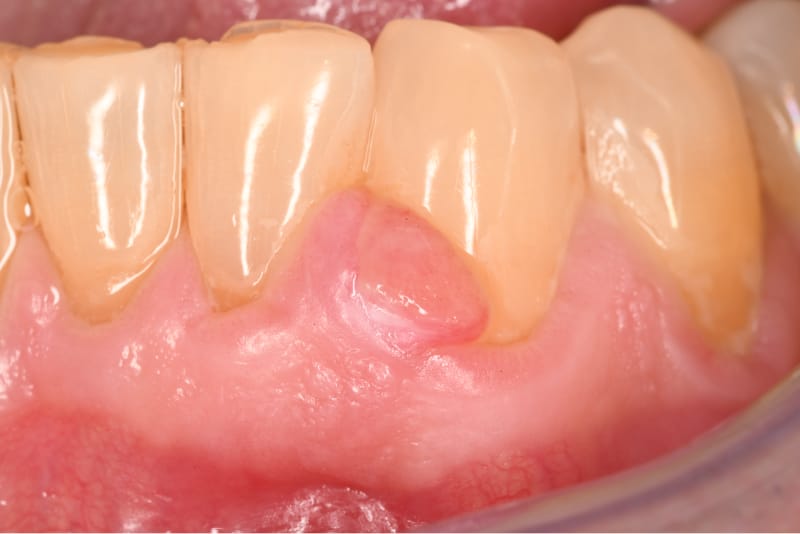

“Gum Bump.”

These are benign lesions that are removed with a simple excision. There is a very low chance of recurrence.